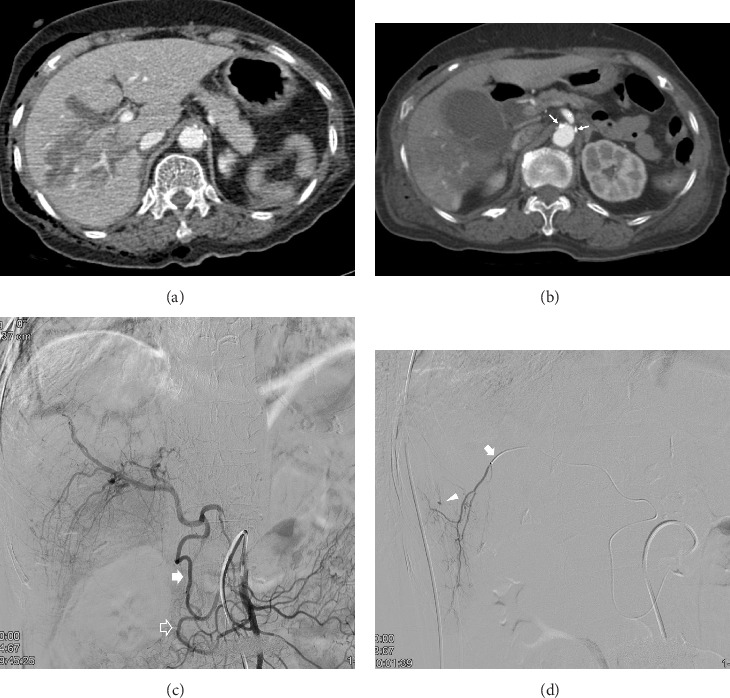

Purpose: This study aimed to evaluate the safety and efficacy of transcatheter arterial embolization (TAE) for hemorrhage control in patients with traumatic liver injury complicated by celiac axis stenosis (CAS). Methods: Nine patients diagnosed with CAS who underwent TAE between January 2012 and December 2024 were included in this retrospective study. Imaging studies were used to assess the vascular anatomy, and clinical outcomes were analyzed, focusing on technical and clinical success rates and complications. Results: All patients achieved technical success with TAE, with a clinical success rate of 77%, and no 30-day mortality. Seven patients had medial arcuate ligament compression, which was identified as the cause of CAS, while two patients had atherosclerosis. Conclusion: TAE is a safe and effective intervention for managing hemorrhage in traumatic liver injury complicated by CAS. Thorough assessment of computed tomography images is crucial for diagnosing the underlying causes of CAS and optimizing catheterization strategies.